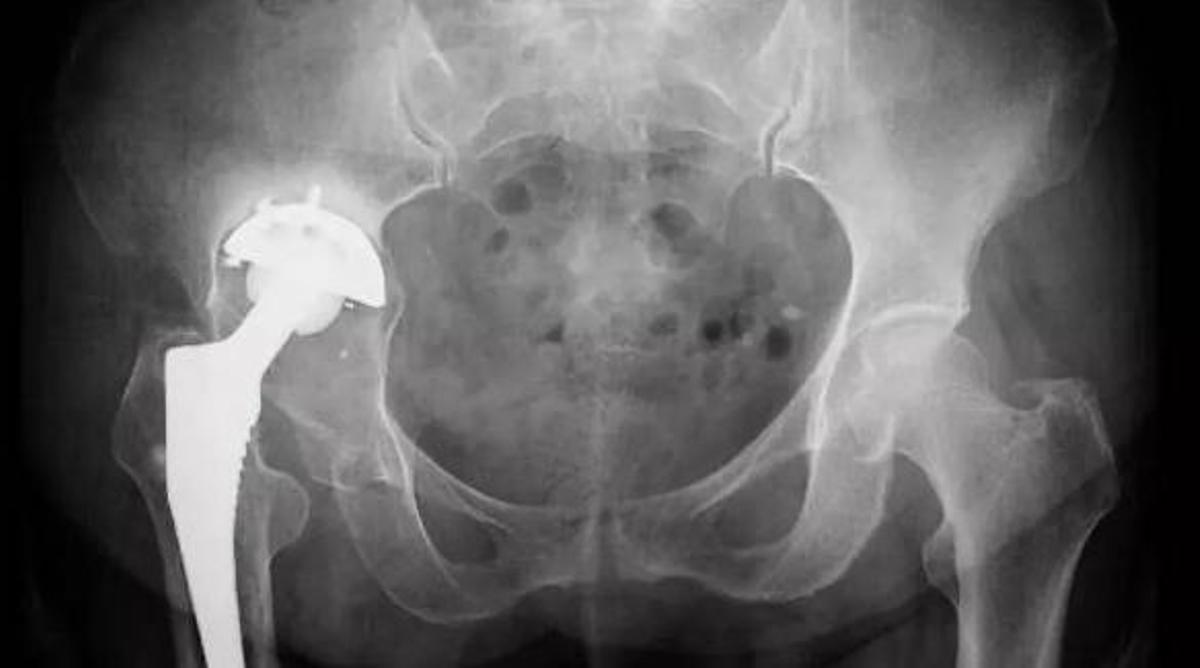

La durada de l'estada hospitalària després d'una artroplàstia total de maluc sol ser d'un a quatre dies

Com es fa l'operació de maluc? / gpointstudio

La durada de l'estada hospitalària després d'una artroplàstia total de maluc (ATC) és d'un a quatre dies. Tot i això, comença a haver-hi un nombre creixent de cirurgians que ara realitzen aquest procediment de forma segura i de forma ambulatòria.